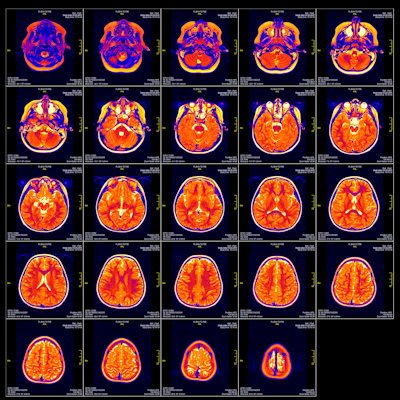

(60772-36) (Pancreas) 4c longitudinal view

Jan 10, 2005